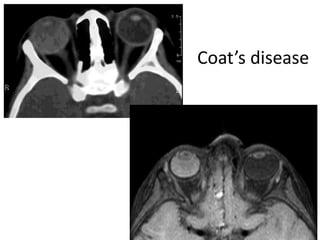

Coat’s disease

• A rare eye disorder: congenital non-hereditary

vascular malformation of the retina

– multiple telangiectatic vessels -> exudate leakage ->

retinal detachment

• A 6-to-8-year-old boy with unilateral leukokoria

• Symptoms occurs when the retina detaches ->

central visual loss

• Findings:

– Increased density of the vitreous

– Normal globe size, lack of calcification